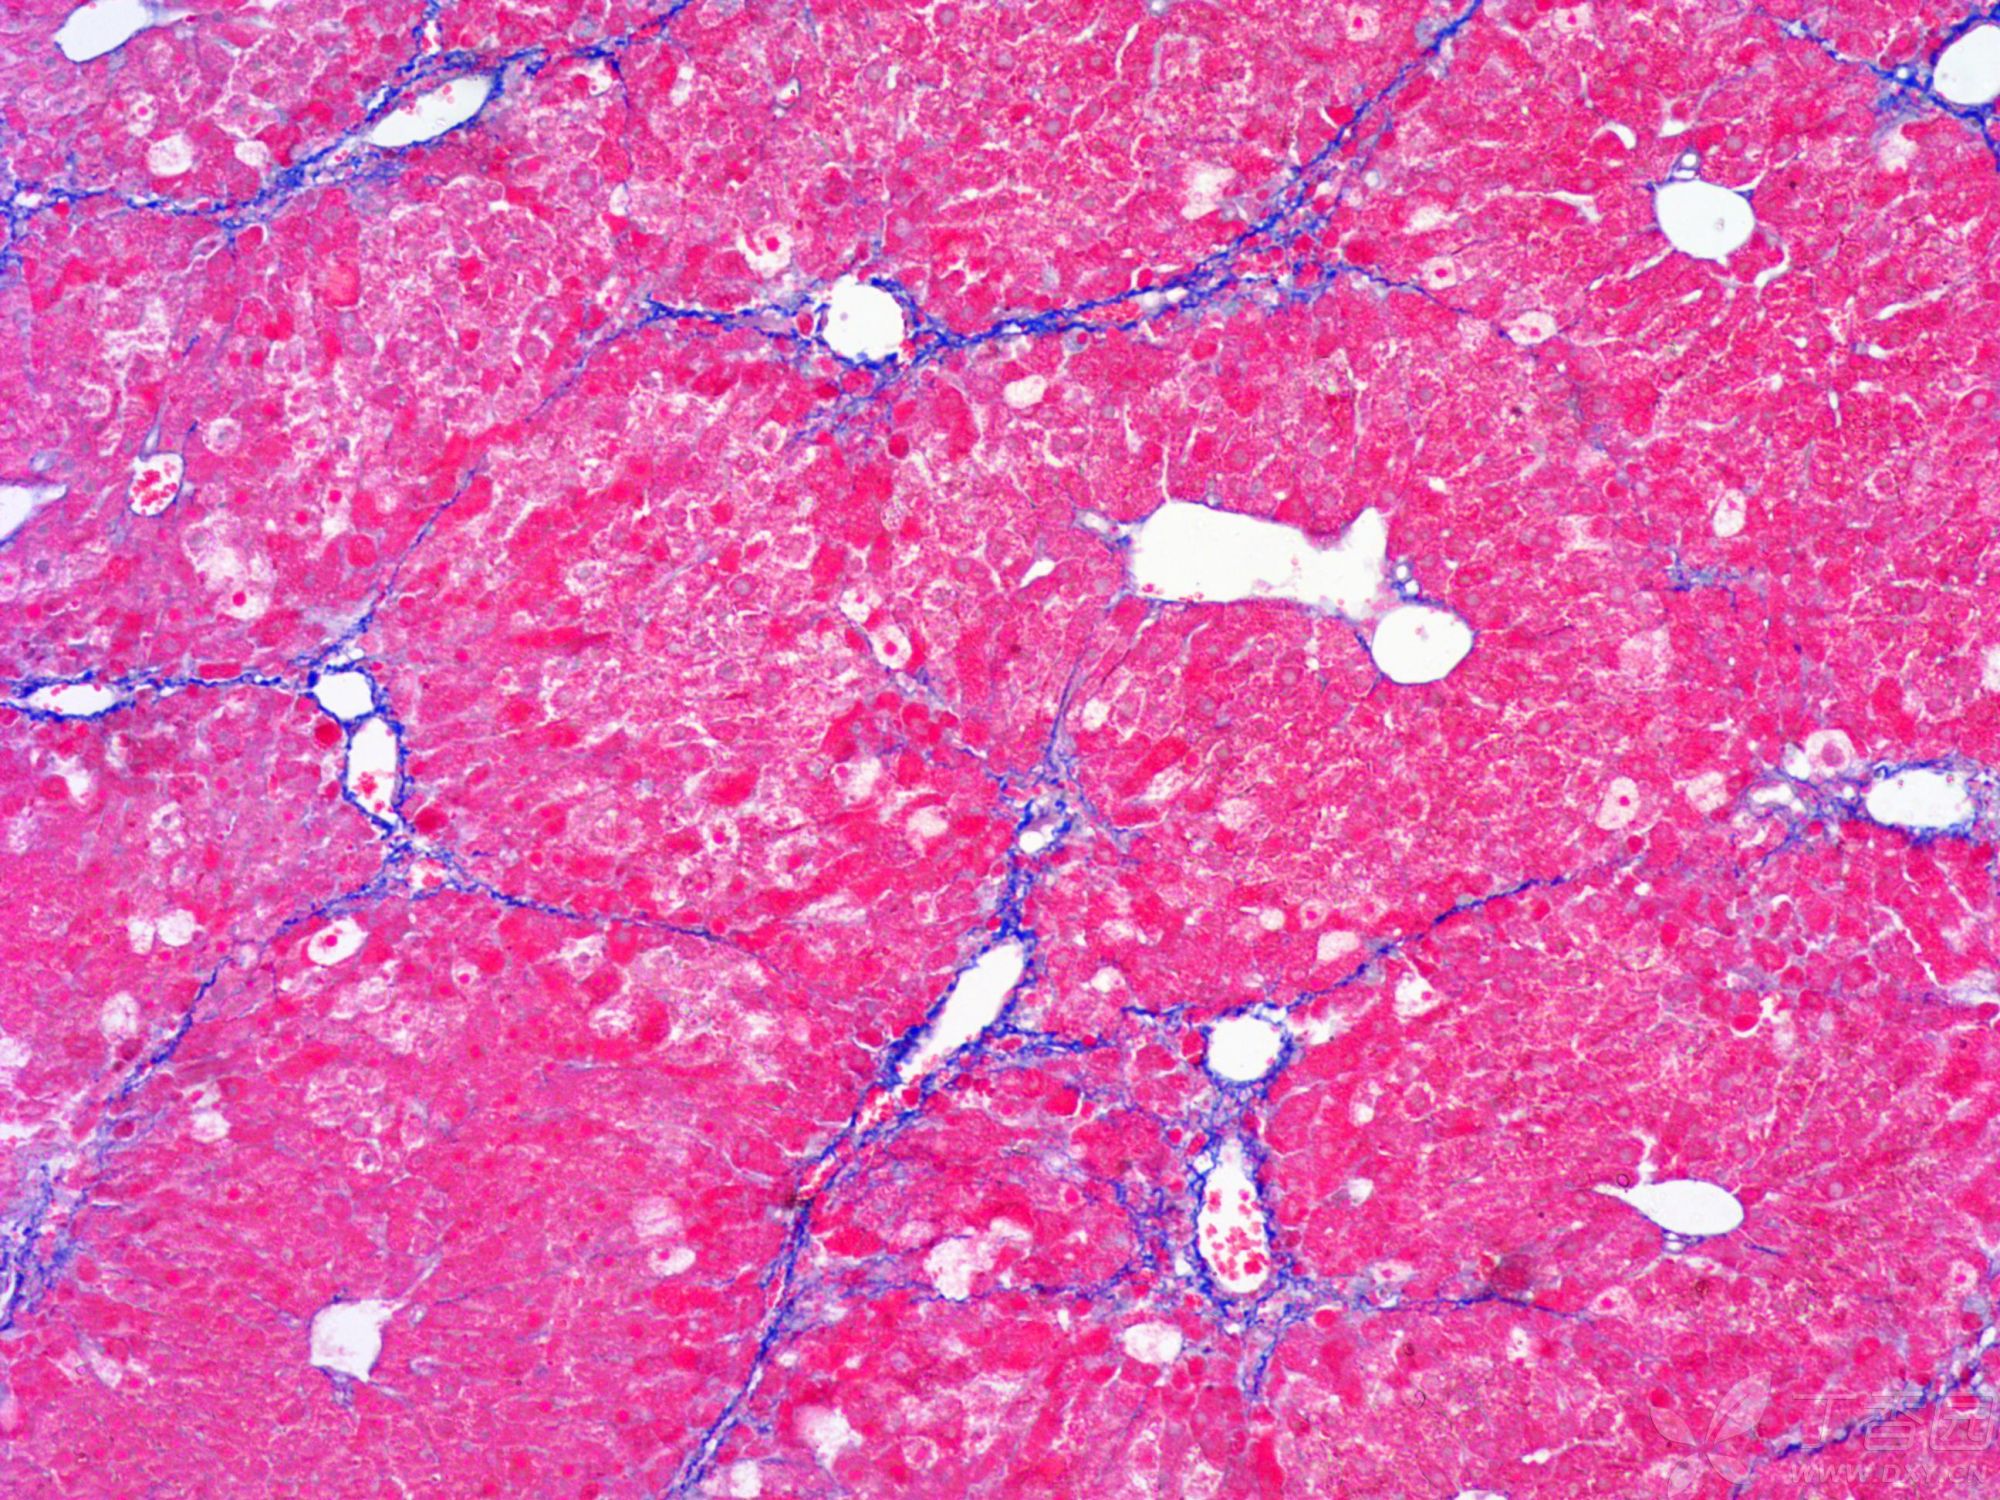

MASSON染色

●觀察與分析:通過顯微鏡觀察染色后的組織切片,分析膠原纖維、肌纖維等組織結(jié)構(gòu)的分布、形態(tài)和排列情況。

小鼠纖維化